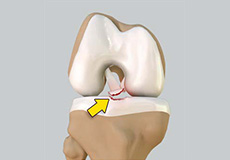

Meniscal Tears

A meniscal tear is a common knee injury in athletes, especially those involved in contact sports. A sudden bend or twist in your knee causes the meniscus to tear.

Within the knee joint, between the femur and tibia, are two C-shaped cartilaginous structures called menisci. Menisci function to provide stability to the knee by spreading the weight of the upper body across the whole surface of the tibial plateau. The menisci help in load-bearing i.e. it prevents the weight from concentrating onto a small area, which could damage the articular cartilage. The menisci also act as a cushion between the femur and tibia by absorbing the shock produced by activities such as walking, running and jumping.

Meniscal Injuries

Meniscal tears are among the commonest injuries to the knee joint. It can occur at any age but are more common in athletes involved in contact sports.